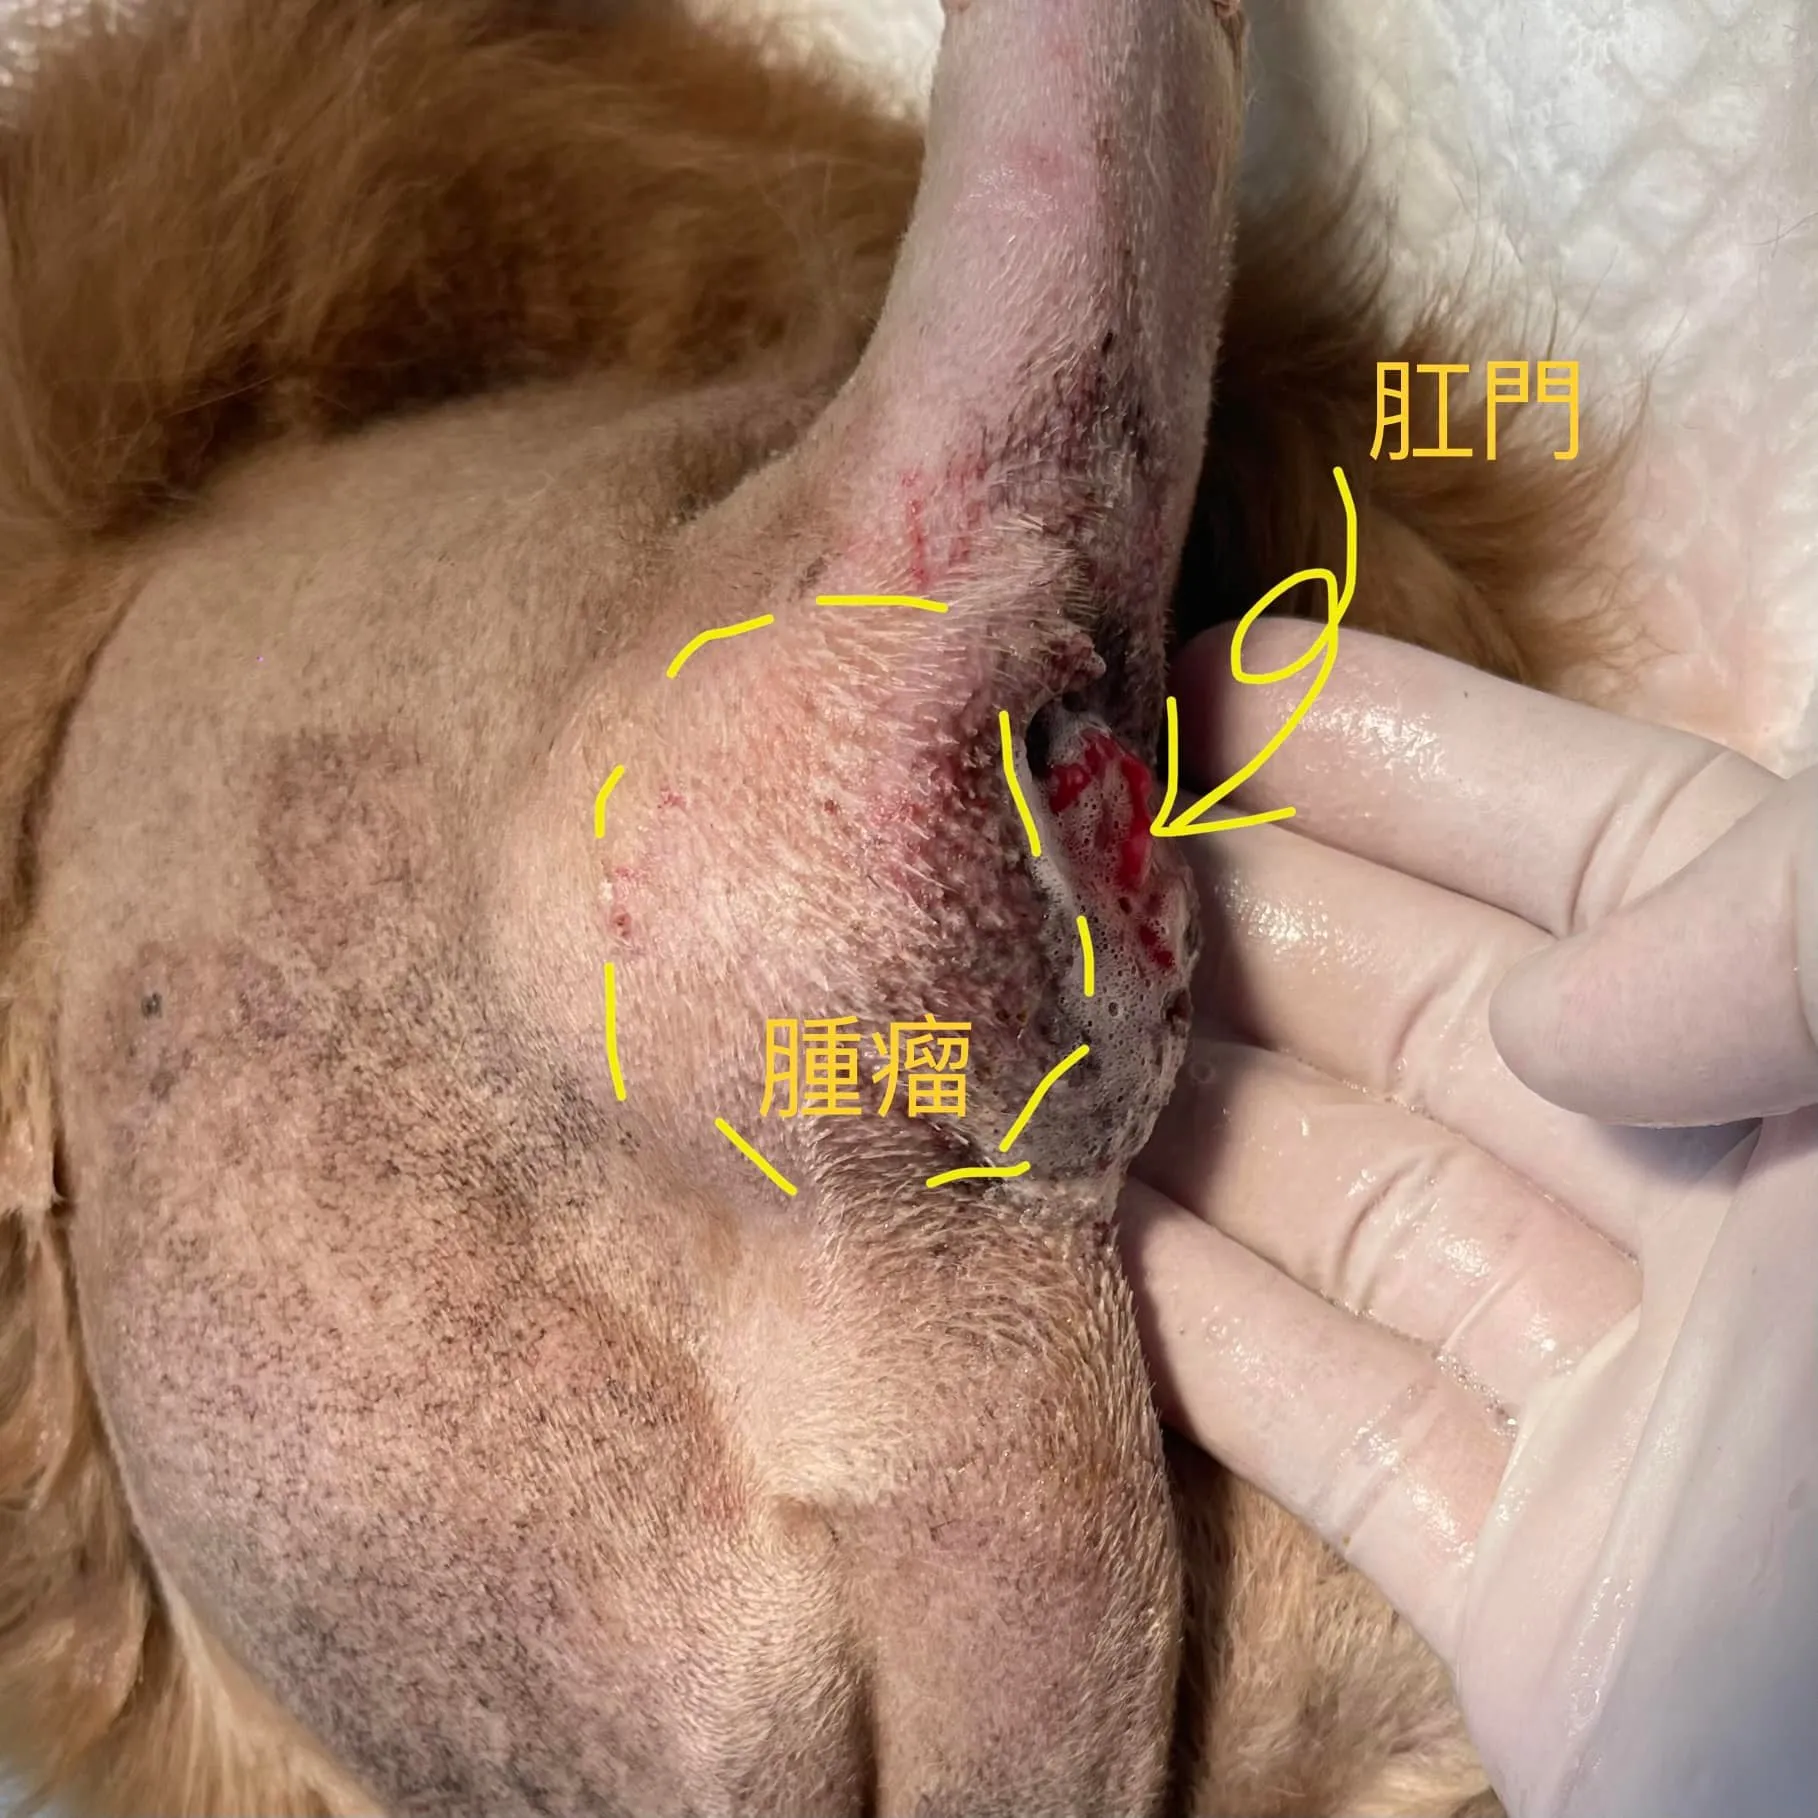

今天這個病例,是曾經在兩年前切除過右側1-3區域乳腺的狗狗,當年也同時進行了子宮卵巢摘除術(OHE), 但過了兩年,既使當時其他乳腺無腫瘤的情況下,進行絕育手術,還是長出了多顆新的乳腺腫瘤! 這次一次將所有腫瘤與剩餘乳腺切除,並且在病理切片發現了兩顆惡性腫瘤 !不過幸好腫瘤都還小,使用這個術式完整切除後,復發率很低,切片結果也顯示不需術後化療,只要定期追蹤胸腔X光片即可!

今天這個病例,是曾經在兩年前切除過右側1-3區域乳腺的狗狗,當年也同時進行了子宮卵巢摘除術(OHE), 但過了兩年,既使當時其他乳腺無腫瘤的情況下,進行絕育手術,還是長出了多顆新的乳腺腫瘤! 這次一次將所有腫瘤與剩餘乳腺切除,並且在病理切片發現了兩顆惡性腫瘤